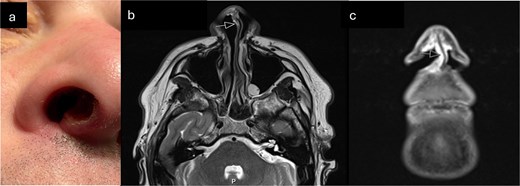

A male in his 30s was referred to our tertiary Rhinology unit with a 6-month history of a nonhealing right nasal vestibule ulceration (Fig. 1a). He described right nasal obstruction, pain radiating to the right eye, occasional serosanguinous rhinorrhea, and intermittent cacosmia. He denied epistaxis or taste disturbance. He was referred from the community after an unsuccessful trial of conservative management with oral and topical antibiotic. He denied weight loss and was otherwise well, with no rhinological history of note. He denied alcohol consumption and previously smoked cigarettes.

(a) Clinical photograph demonstrating ulcerated lesion of anterior membranous nasal septum (b) T2 axial MRI-arrow indicates soft tissue thickening of columella (c) Coronal STIR MRI sequence—high signal soft tissue thickening extending from columella to right nasal sill (indicated by arrow).

Anterior rhinoscopy demonstrated a 1 cm ulcer on the right anterior membranous septum, extending posteriorly to the cartilaginous septum and superiorly under the upper lateral cartilage. The edge was rolled, crusty, and had a sloughy base overlying visible perichondrium. Rigid endoscopy revealed no further local progression, and no other lesions of concern. There was no cervical lymphadenopathy.